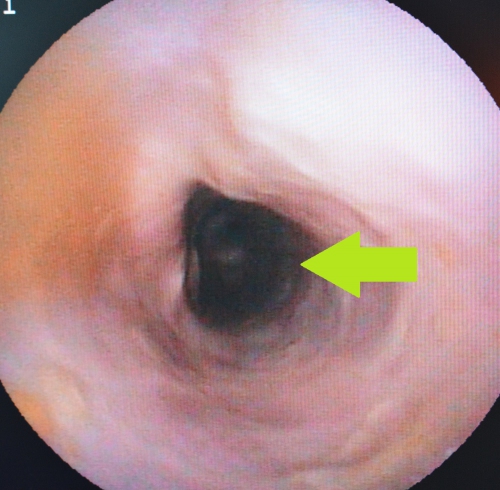

下の2枚の写真は胸部食道のほぼ同じ場所を撮影した内視鏡画像です。左写真が正常な食道、右写真が重度の慢性食道炎の結果生じた食道狭窄の内視鏡写真です。左の正常と比べると食道の粘膜に激しい変化を生じているのが確認できます。